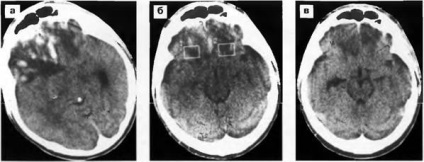

Ábra. 20. Dynamics zúzódás elváltozások (vérzéses impregnáló) CT. és - CT 15 nap traumás agysérülés után: több gócok növekvő sűrűségű (vérzés) és sűrűségét alacsonyan fekvő területeken lobnobazalnyh osztályok, több a jobb oldalon, és a tömörítés a jobb oldali kamrába; b -KT 27 nappal a sérülés után: szakaszai sűrűség csökkenése és izolált zsebek növekvő sűrűségű a fronto-bazális, inkább a jobb oldali; in - CT után 2,5 hónappal. sérülés után: a sűrűsége alacsonyan fekvő területeken a fronto-bazális aszimmetriája alsó szarvak az oldalsó agykamrák.

Ábra. 18. zúzódás gócok a bazális halántéklebeny mindkét oldalán, és a frontális (többnyire jobb) egy gyermek 10 éves. CT (a, b, c) 3 órán traumás agysérülés után. vérömlenyek sűrűség növekszik, a periférián - alacsony sűrűségű terület.